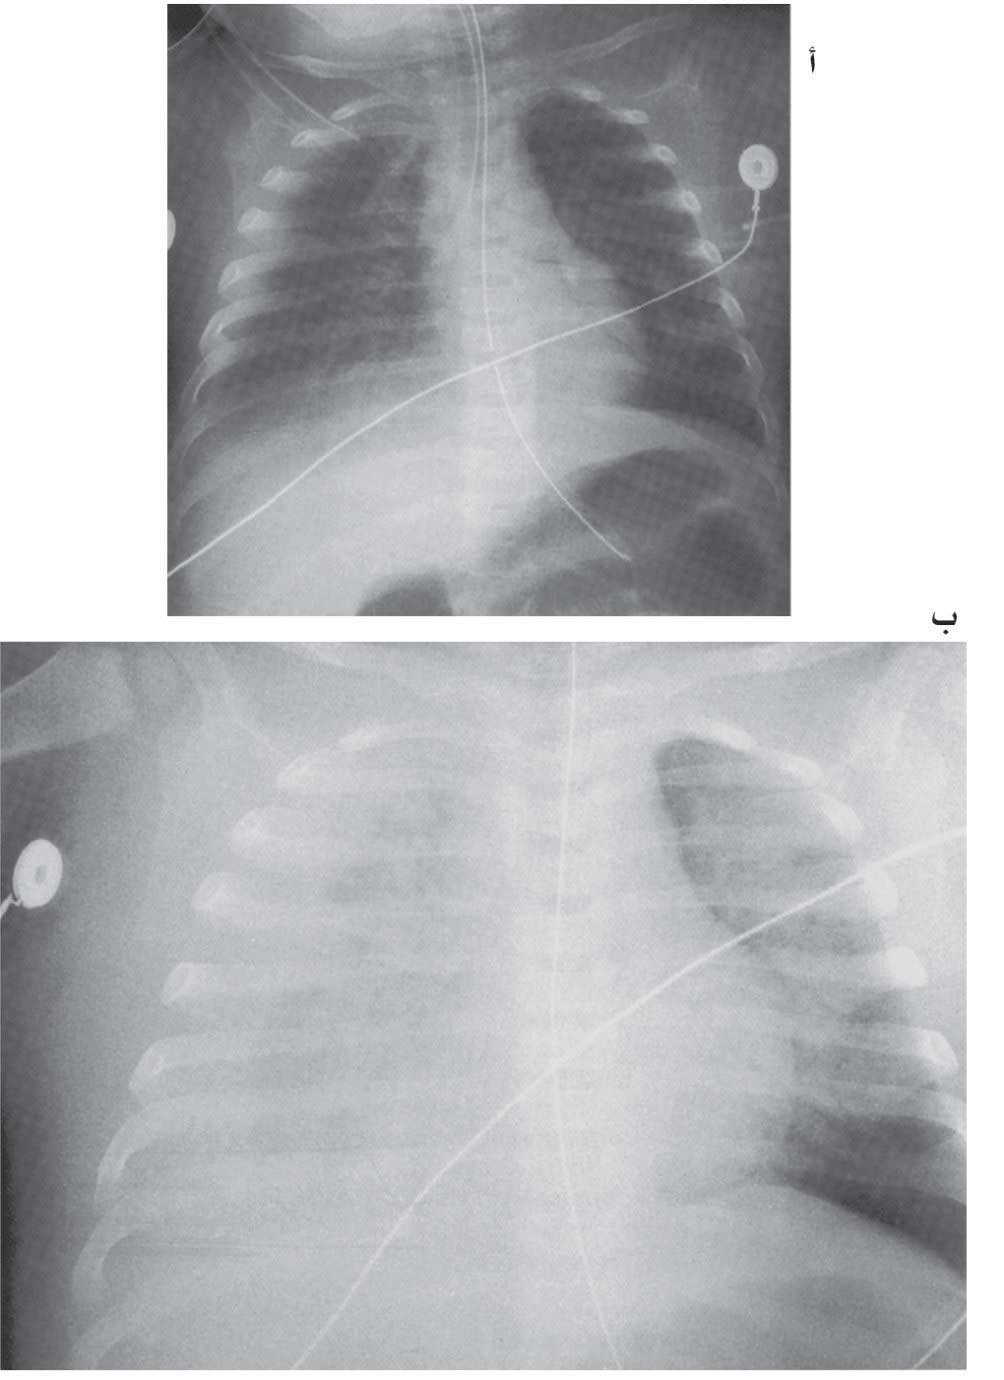

| الشكل (6) أ- ارتشاحات خلالية منتشرة لدى رضيع بعمر 8 أشهر لديه ذات رئة بالعنقوديات المذهبة ب- بعد 6ساعات من الصورة الأولى ازدادت وبشكل نوعي الارتشاحات البارانشيمية مع غياب حدود الحجاب الحاجز الأيمن بسبب انصباب الجنب الأيمن. |

تتطور الأعراض بعد يوم إلى ثلاثة أيام من الحرارة والسعال على نحو حاد وسريع فتبدو أعراض تنفسية شديدة، كالخراخر وتسرع التنفس والسحب الوربي وتحت الأضلاع الشديد والزرقة والقصور التنفسي الحاد وتتدهور الحالة سريعاً سريرياً وشعاعياً كما هو واضح في الصورتين الشعاعيتين للطفل نفسه بعمر 8 أشهر مصاب بذات رئة بالعنقوديات المذهبة.

التظاهرات الشعاعية: تراوح بين ارتشاحات خلالية ثنائية الجانب (في ذات الرئة الثانوية)، أو وحيدة الجانب (تكثف فصّي أحادي الجانب في الإصابة الأولية).

تحدث الكيسات الرئوية في 45%-65% من المرضى وقد يحدث انصباب جنب في 70% من الحالات مع احتمال حدوث مضاعفات باكرة وسريعة كالريح الصدرية، أو متأخرة كالتليّف الصدري والتوسع القصبي.

وقد تستغرق هذه التغيرات الشعاعية أسابيع عديدة كي تنحسر أو تزول.

التشخيص: التبدلات الشعاعية المشاهدة في صورة الصدر تكاد تكون خاصة بذات الرئة بالعنقوديات، إضافة إلى التطور السريري والشعاعي السريع نحو الأسوأ.